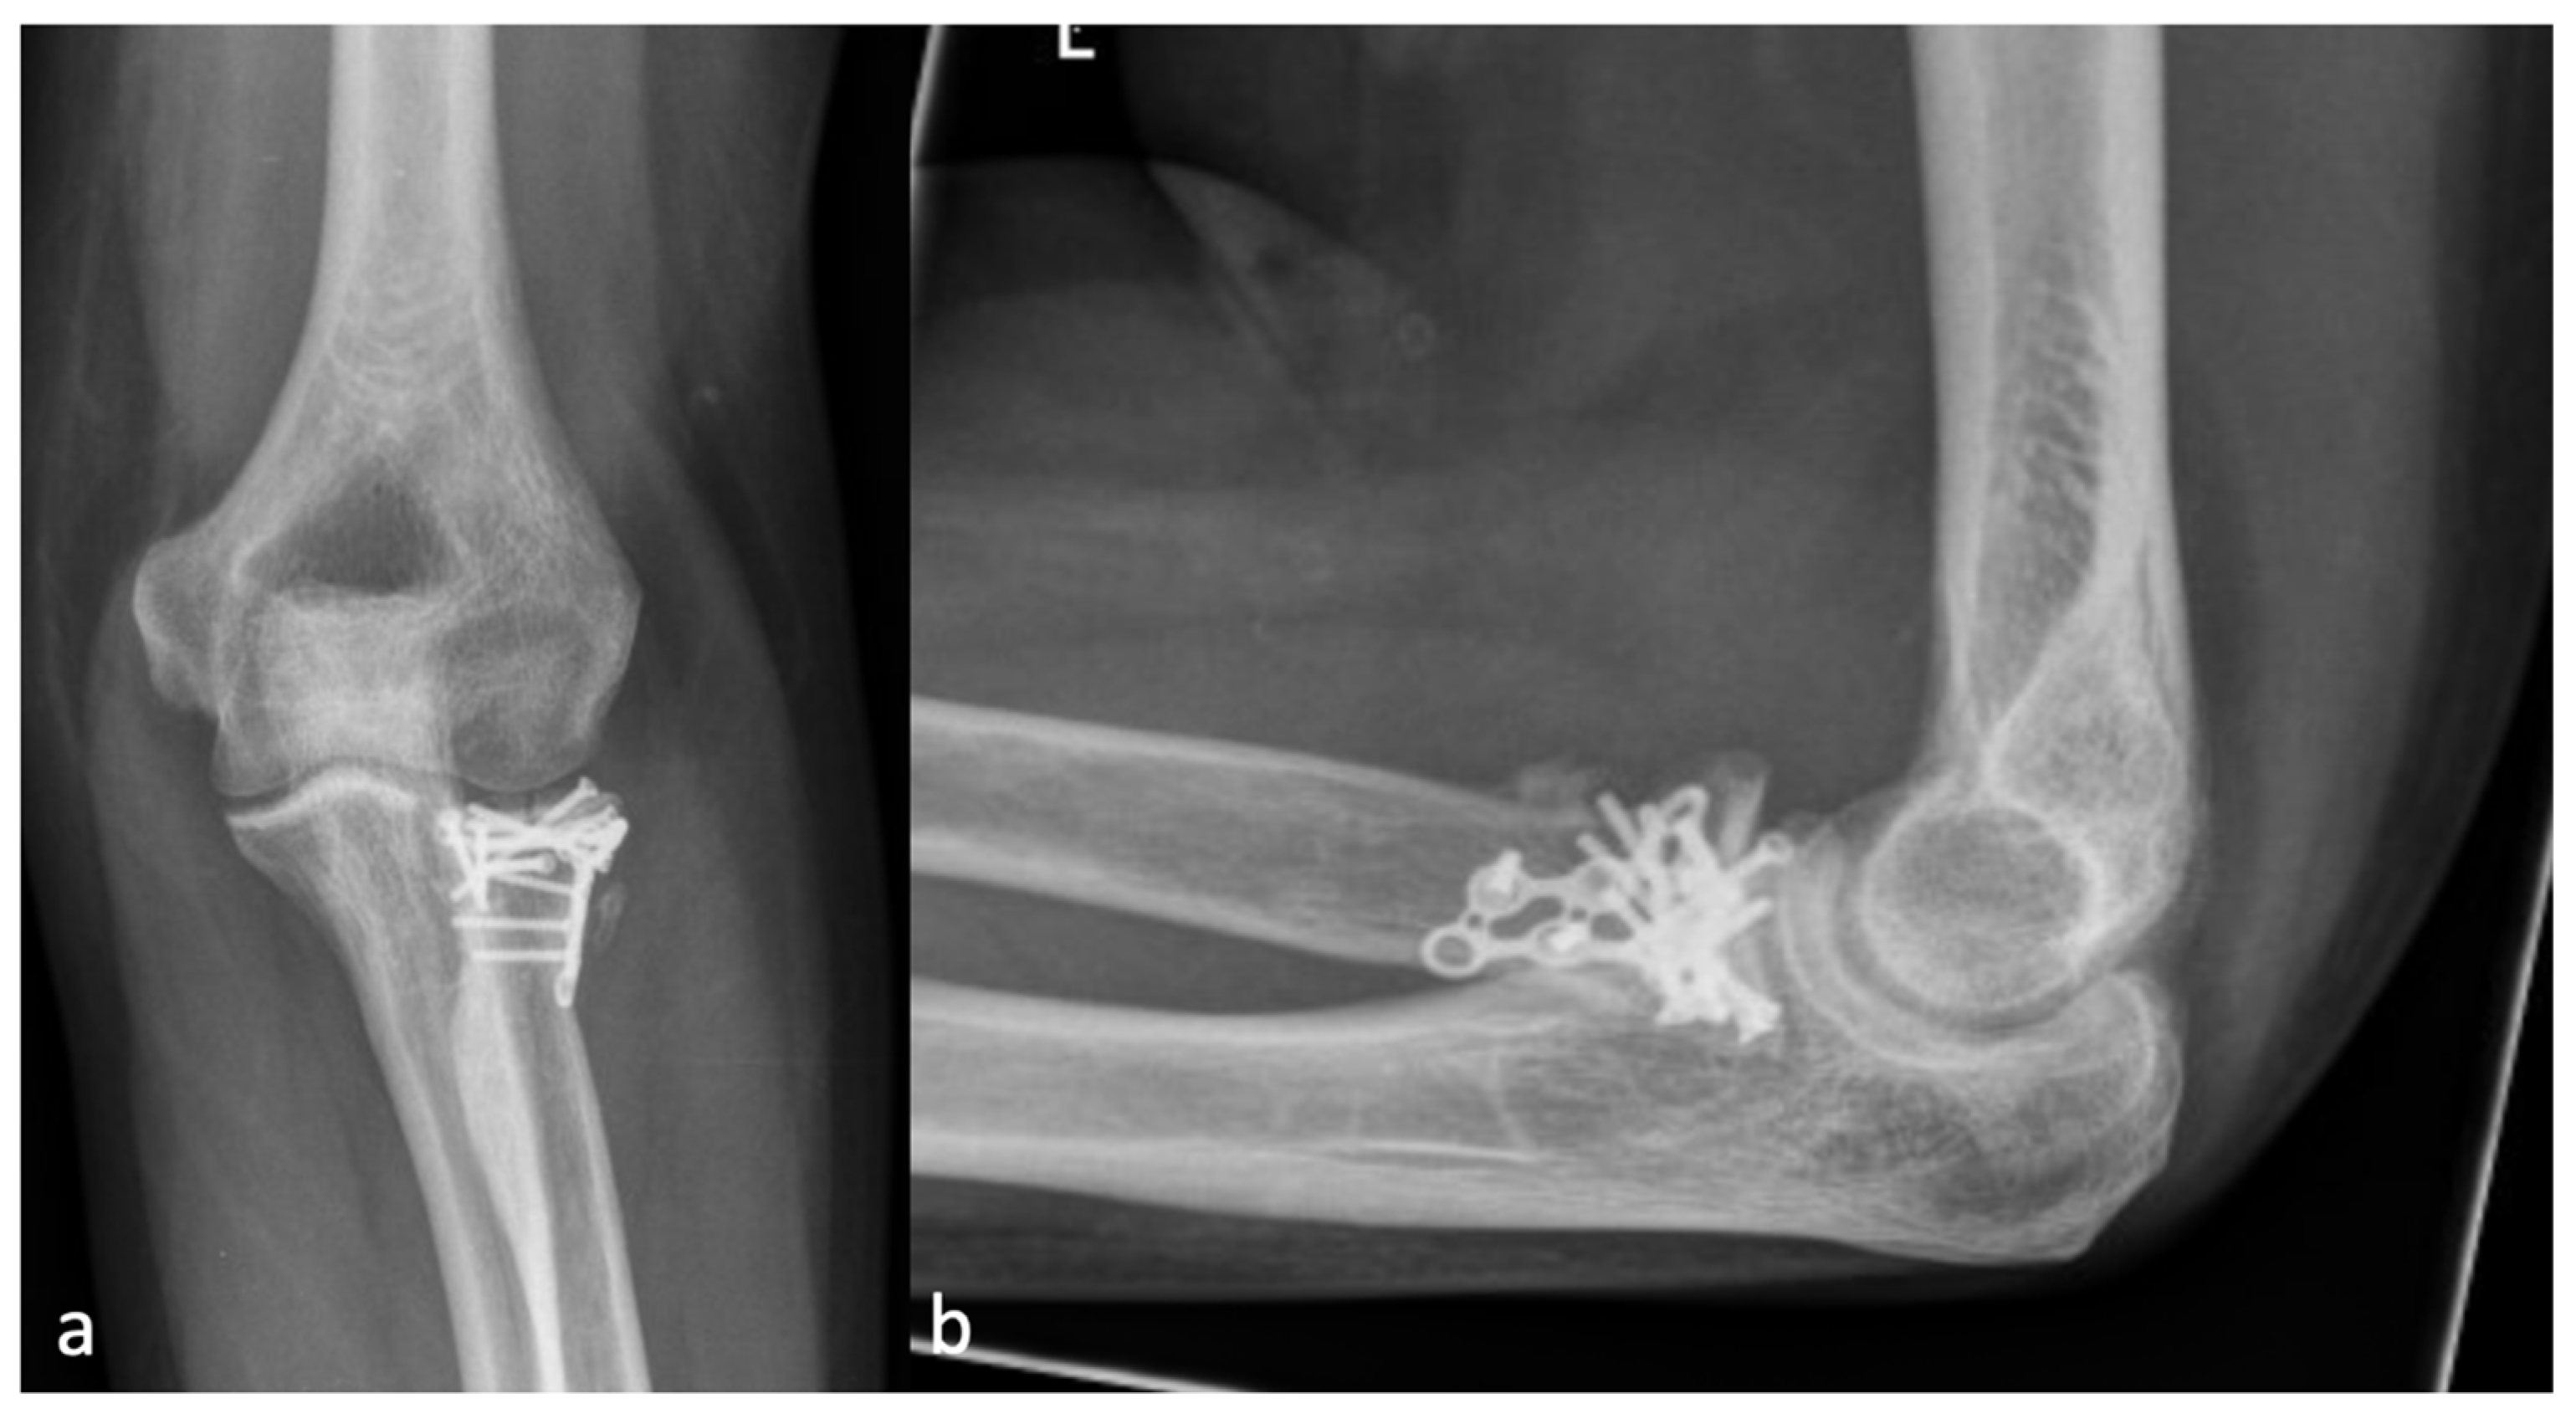

2.2. Radiographic Assessment

2.3. Classification

3.2. Relationship between Injury Localization and the Localization of HO

3.3. Correlation between the Application of Ossification Prophylaxis and the Severity of HO

4.1. Classification